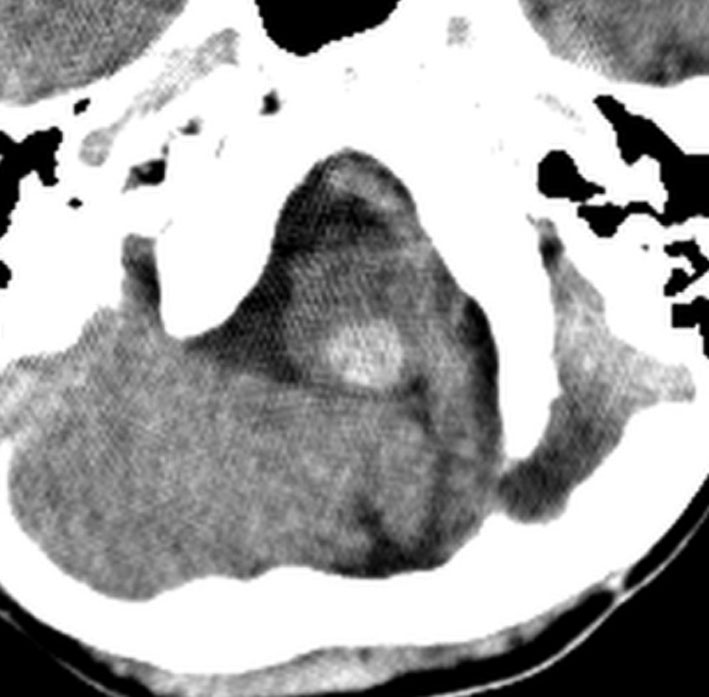

20年以上前のことですが,髄芽腫の1歳6ヶ月の子どもに25グレイの全脳照射をしました。これは15年後のCTです。

脳の萎縮は目立ちません。認知機能は低いのですが支援を受けて学校へ行けています。下垂体機能は低下して成長ホルモンなどの補充をして普通に暮らせています。

CTで,両側の大脳基底核(被殻と淡蒼球)と視床後部に石灰化がみられます。乳幼児期に放射線治療を受けた子どもに見られるものです。